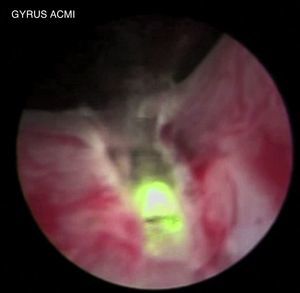

En primer lugar se enuclea el lóbulo medio, realizando una incisión en la posición de las 5 del reloj desde el cuello vesical hasta el límite marcado a nivel del verum montanum, profundizando la fotovaporización del tejido hasta la cápsula prostática, la cual se identifica como una capa blanquecina con vasos superficiales. Se realiza el mismo procedimiento en el radio de las 7 del reloj (fig. 1).

Posteriormente se inicia la disección del lóbulo medio de manera retrógrada con un movimiento pendular por debajo, apoyado con la fotovaporización láser para mantener adecuada hemostasia, separándolo de la cápsula prostática hasta enuclearlo y desplazado hacia la vejiga (fig. 2).